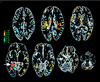

Participation of two medial temporal lobe structures, the hippocampal region and the amygdala, in long-term declarative memory encoding was examined by using positron emission tomography of regional cerebral glucose. Positron emission tomography scanning was performed in eight healthy subjects listening passively to a repeated sequence of unrelated words. Memory for the words was assessed 24 hr later with an incidental free recall test. The percentage of words freely recalled then was correlated with glucose activity during encoding. The results revealed a striking correlation (r = 0.91, P < 0.001) between activity of the left hippocampal region (centered on the dorsal parahippocampal gyrus) and word recall. No correlation was found between activity of either the left or right amygdala and recall. The findings provide evidence for hippocampal involvement in long-term declarative memory encoding and for the view that the amygdala is not involved with declarative memory formation for nonemotional material.